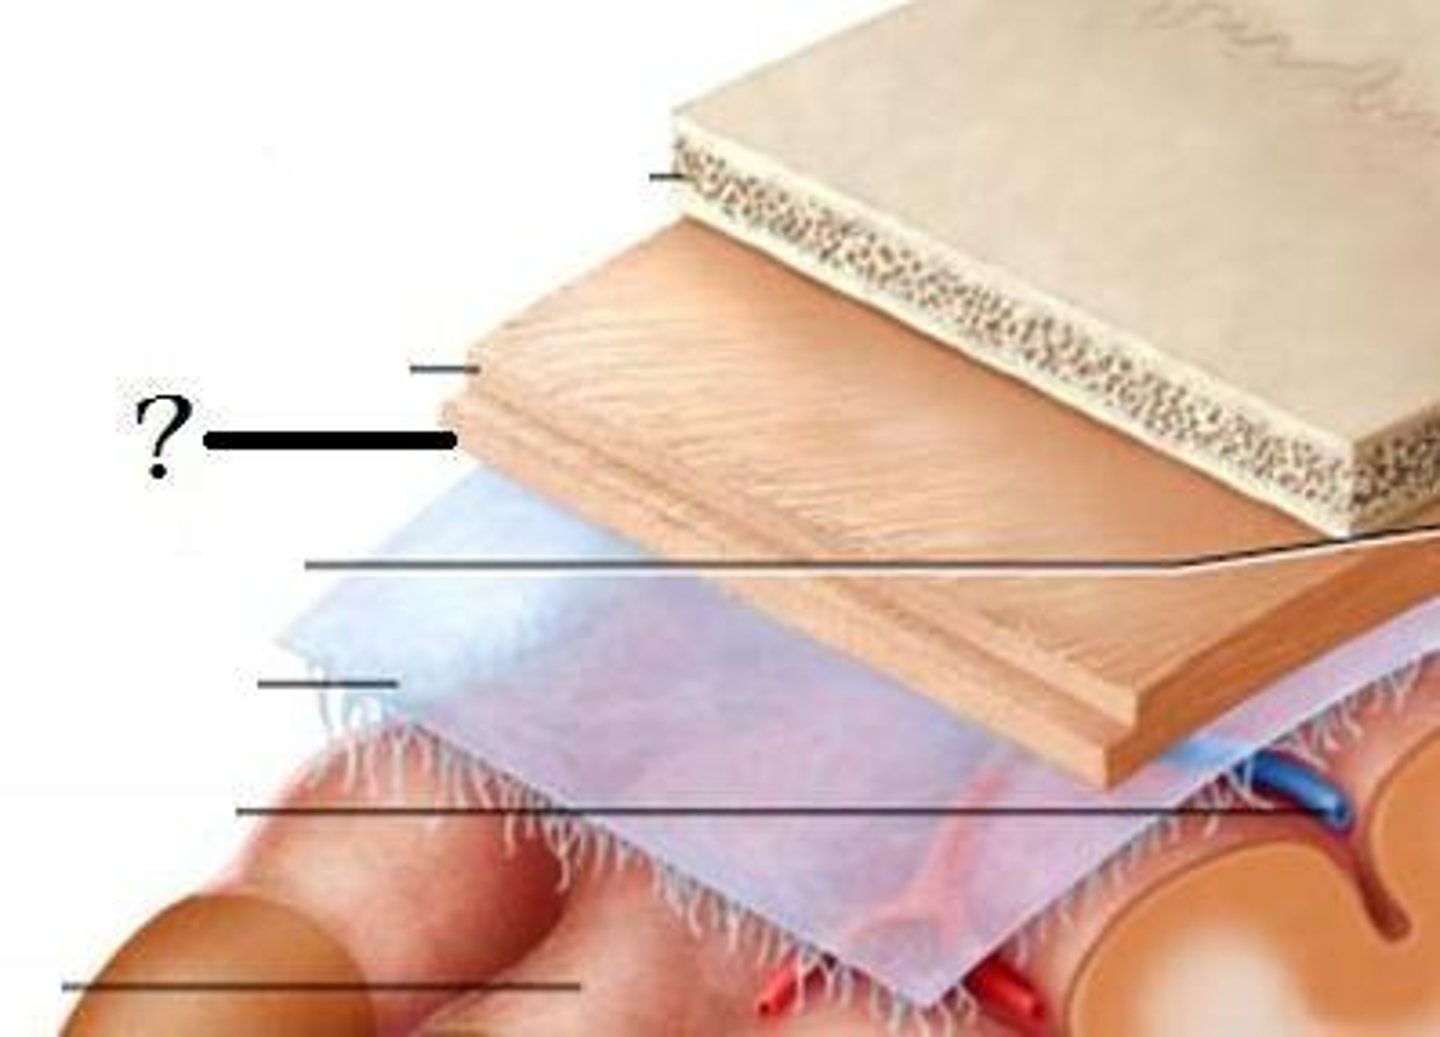

meninges

•Three connective tissue layers

•Separate and support soft tissue of brain

•Enclose and protect blood vessels supplying the brain

•Help contain and circulate cerebrospinal fluid

•From deep to superficial (PAD to protect the brain)

--Pia mater

--Arachnoid mater

--Dura mater

dura mater (brain)

thick, outermost layer of the meninges surrounding and protecting the brain and spinal cord

arachnoid mater (brain)

middle web-like layer of the meninges

pia mater (brain)

thin, delicate inner membrane of the meninges

spinal meninges

dura mater, arachnoid mater, pia mater (PAD to protect the spinal cord from deep to superficial)

dura mater (spinal cord)

thick, outermost layer of the meninges; 5 on image

arachnoid mater (spinal cord)

middle weblike layer of the meninges; 4 on image

pia mater (spinal cord)

thin, delicate inner membrane of the meninges; 3 on image